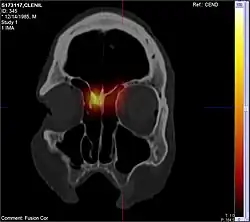

CT scan images after application of radioactive laced nasal steroids using long nozzle. Note the reach of the medication into the area where nasal polyps originate

Endoscopic sinus surgery, advocated and popularized by Professor Stammberger, is often very effective for most people, providing rapid symptom relief. Endoscopic sinus surgery is minimally-invasive and is done entirely through the nostril with the help of a camera. Surgery should be considered for those with complete nasal obstruction, uncontrolled runny nose, nasal deformity caused by polyps or continued symptoms despite medical management.[7] Surgery serves to remove the polyps as well as the surrounding inflamed mucosa, open obstructed nasal passages, and clear the sinuses. This not only removes the obstruction caused by the polyps themselves, but allows medications such as saline irrigations and topical steroids to become more effective.[19] It has been suggested that one of the main objectives in sinus surgery for polyps is to allow delivery of the steroids into those areas of the sinuses where polyps develop, namely, the ethmoid sinuses. Specially designed long nozzles had been developed to use postoperatively to deliver steroids into those areas after sinus surgery for polyps.[20]